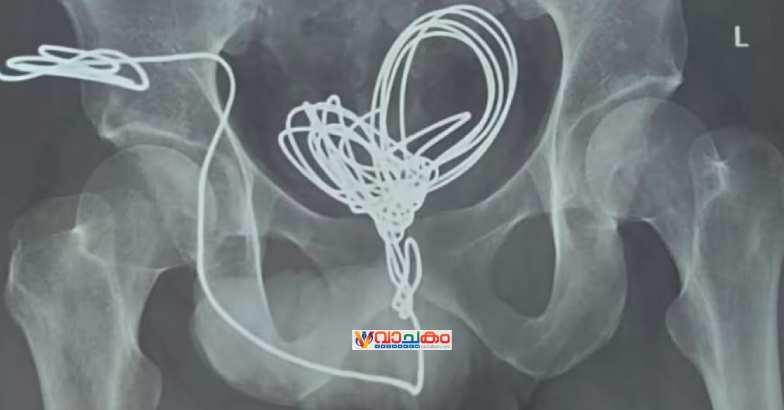

തിരുവനന്തപുരം: മൂന്ന് മീറ്ററോളം ഇലക്ട്രിക് വയര് മൂത്രനാളിയിലൂടെ കുത്തിക്കയറ്റി യുവാവ്. തിരുവനന്തപുരം സ്വദേശിയായ 25കാരനാണ് മൂന്ന് മീറ്ററോളം നീളമുള്ള ഇലക്ട്രിക് ഇന്സുലേഷന് വയര് മൂത്രനാളിയിലൂടെ കുത്തിക്കയറ്റിയത്.

ആശുപത്രിയിലെത്തിച്ച യുവാവിന്റെ വയറ്റില് നിന്ന് വയര് ശസ്ത്രക്രിയയിലൂടെ പുറത്തെടുത്തു. യൂറോളജി വിഭാഗത്തില് വയര് തുറന്ന് നടത്തിയ ശസ്ത്രക്രിയയിലൂടെയാണ് പല കഷ്ണങ്ങളായി മുറിച്ച് ഇലക്ട്രിക് വയര് പുറത്തെടുത്തത്.

തിരുവനന്തപുരം മെഡിക്കല് കോളേജിലെത്തിക്കുമ്പോള് വയര് മൂത്ര സഞ്ചിയില് കുരുങ്ങിക്കിടക്കുന്ന നിലയിലായിരുന്നു. എന്നാല് യുവാവ് ഇത് ചെയ്തതിന്റെ കാരണം വ്യക്തമല്ലെന്ന് അധികൃതര് പറഞ്ഞു.

ശസ്ത്രക്രിയ രണ്ടര മണിക്കൂറോളം നീണ്ടു. ശസ്ത്രക്രിയക്ക് ശേഷം തീവ്രപരിചരണ വിഭാഗത്തില് ചികിത്സയില് കഴിയുന്ന യുവാവ് സുഖം പ്രാപിച്ചു വരുന്നതായി ആശുപത്രി അധികൃതര് അറിയിച്ചു.